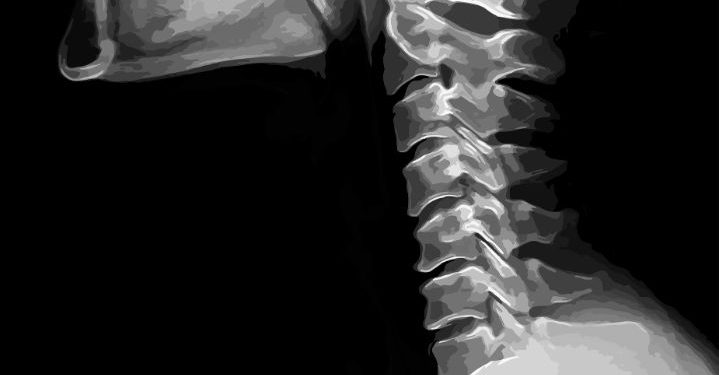

The anatomy of the head and neck is complex. Treatment is best coordinated by a multidisciplinary team, which includes a radiation oncologist, a head and neck surgeon, and other specialists. Doctors may perform tests such as x-rays, positron emission tomography, and computed tomography to determine the extent of the tumor. Additionally, they may counsel the patient to stop smoking and undergo blood tests.

Often, a CT scan can be used to evaluate the extent of the cancer and to detect metastases. It is also useful for identifying the presence of lymphatic involvement. Other imaging techniques can be used to screen for distant metastases. Combined-modality treatments such as radiation, chemotherapy, and surgery are often recommended for large infiltrative lesions. Adding chemotherapy to adjuvant radiation therapy improves regional control of the tumor.